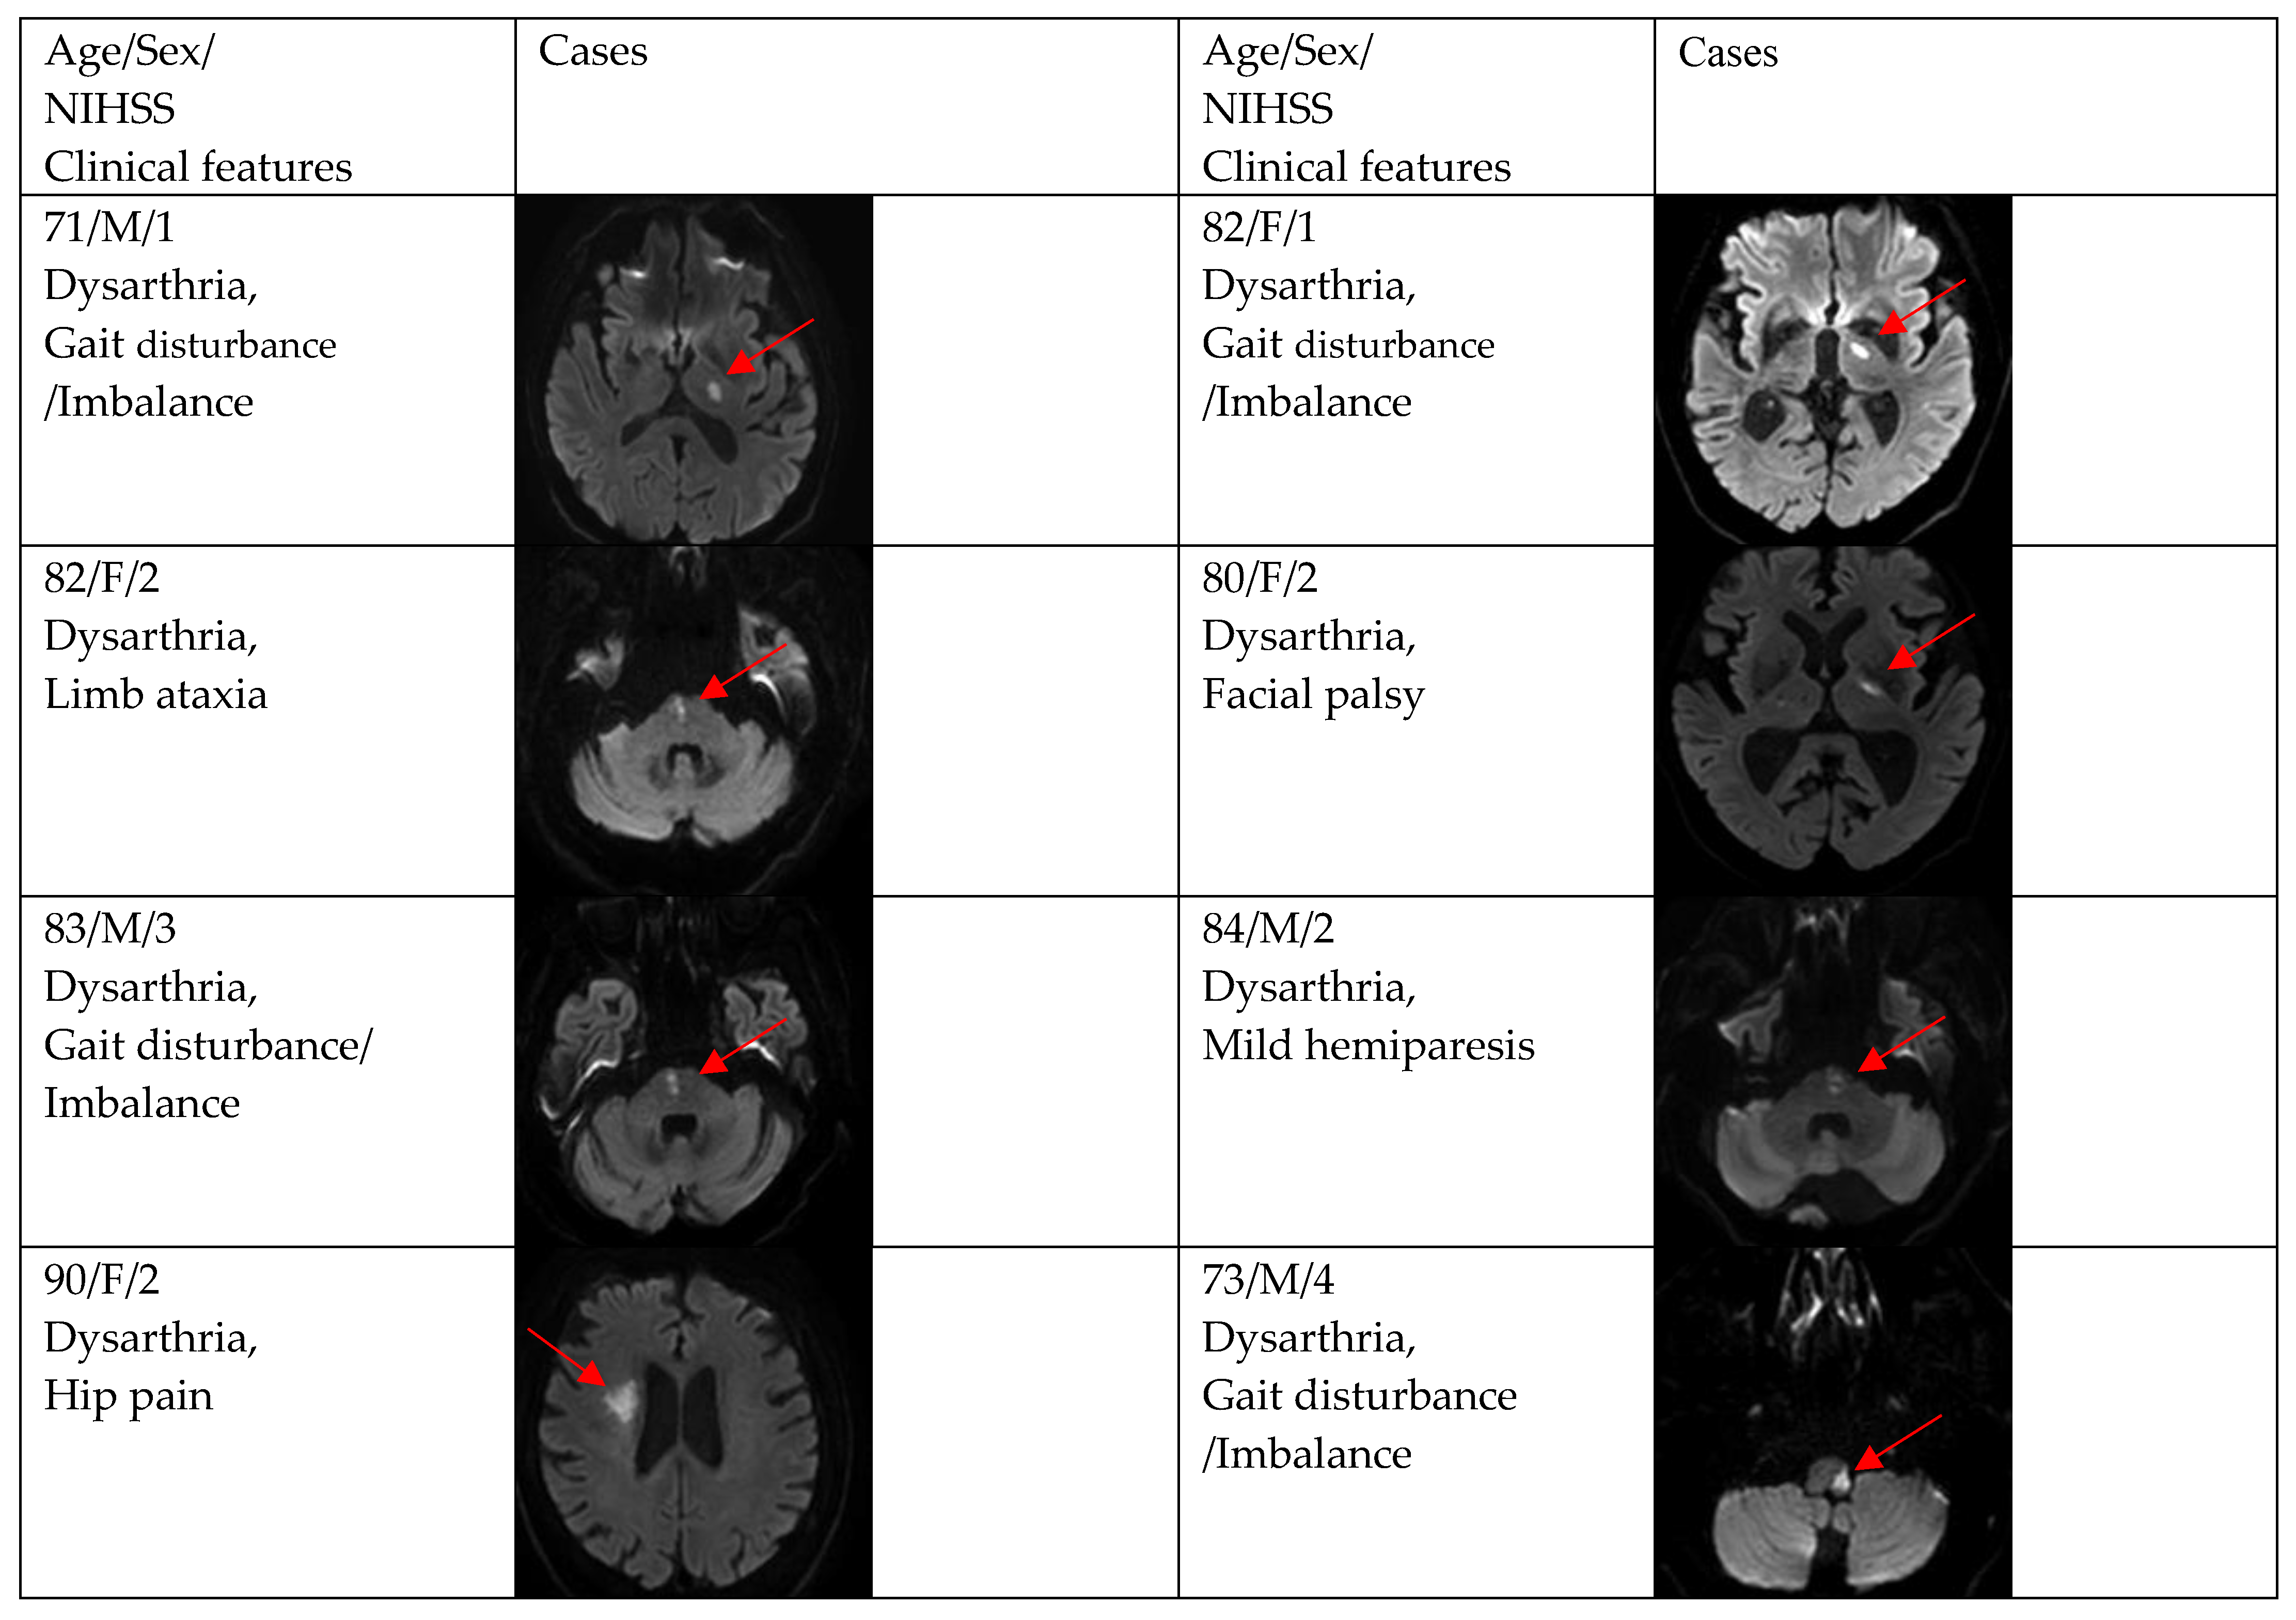

| Gait disturbance/imbalance | 9 (19.2) | 1 (7.7) | 8 (23.5) |

| Facial palsy | 8 (17.0) | 1 (7.7) | 7 (20.6) |

| Mild hemiparesis | 5 (10.6) | 2 (15.4) | 3 (8.8) |

| Limb ataxia | 3 (6.4) | 0 (0.0) | 3 (8.8) |